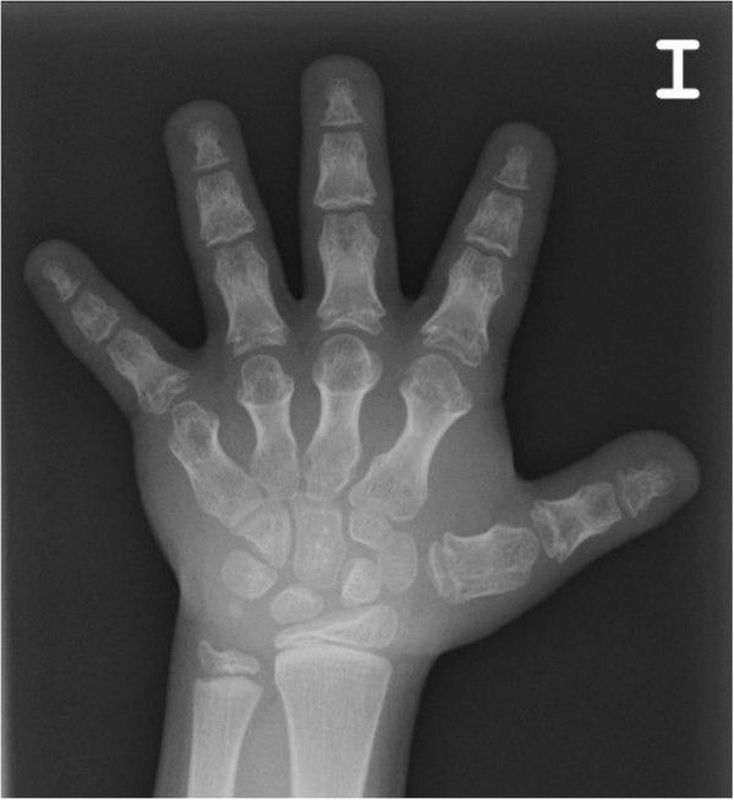

Acrodysostosis is a rare genetic disorder characterized by skeletal malformations, growth delays, short stature, and distinctive facial features caused, in part, by underdeveloped (hypoplastic) of certain facial bones, particularly those in the middle portion of the face. A characteristic symptom is abnormally small hands and feet with short, stubby fingers and toes that may affect all or some of the fingers and toes. Some affected children have varying degrees of intellectual disability; in other children intelligence is unaffected. Some children experience resistance to certain hormones, which means that the tissues of the body do not respond to the hormone in question despite normal or high activity levels of the hormone. Acrodysostosis may be caused by mutations in the PRKAR1A gene (type 1) or the PDE4D gene (type 2). These mutations usually occur sporadically without a positive family history; mutations in PDE4D can be inherited in an autosomal dominant manner. It is likely that additional forms of acrodysostosis exist; caused by as-yet-unidentified gene mutations.